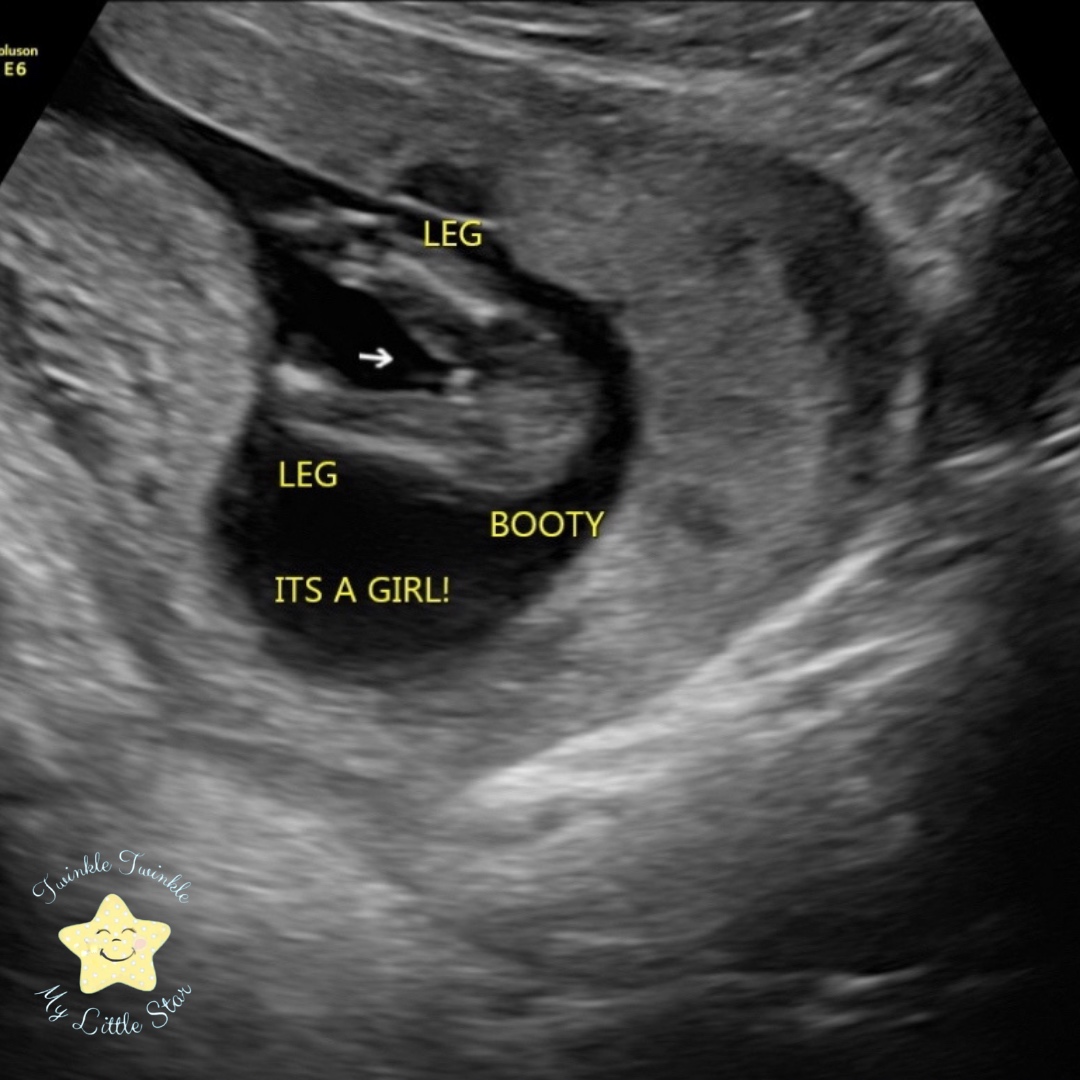

We are an elective and diagnostic prenatal ultrasound clinic serving the Los Angeles area and surrounding cities. We offer a variety of prenatal services such as – pregnancy confirmation ultrasounds, wellness checks, gender confirmations starting at 6 weeks, genetic testing starting at 10 weeks, 3D/4D HD LIVE. If you are on bed rest or prefer to stay home, we can also come to you with our mobile ultrasound machine.

Our GE Voluson E6 BT17 is one of the most popular and respected machines for OB/GYN. It is in the best class in woman imaging. The Voluson E6 BT17 ultrasound machine has excellent workflow, great ergonomics, and many advanced OB/GYN features, including its extraordinary 4D HD LIVE imaging. It has an intuitive 10.4-inch touch screen that reduces procedure time and Scan Assistant, which further optimizes workflow in several obstetric scans. Overall, it is a healthier choice for expecting mothers. For examples of the image quality in 2D, 3D & 4D HD LIVE, we invite you to view our photos in our Gallery tab. Check out the few that we have below.